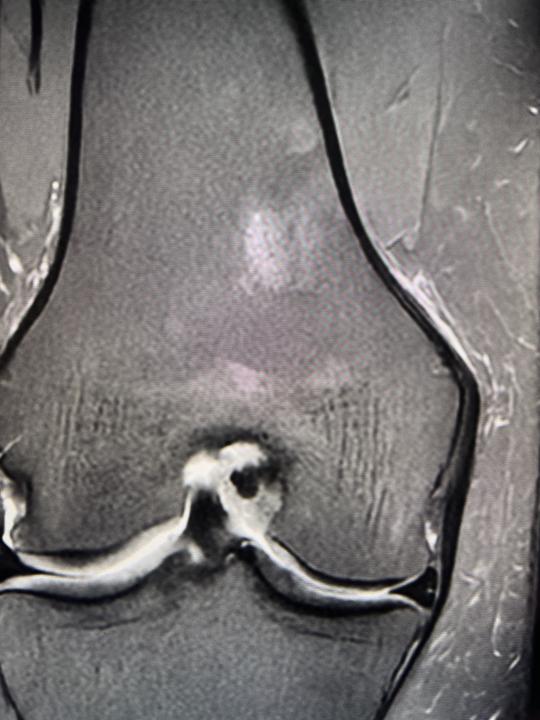

Bone marrow

There is a case of 45 yo female. The examination was done due to injury in 15th of March. I have a question about bone marrow reconvertion. I can see T1 low signal involved partially subchondral layers of tibial and femoral condyles. Any suggestions about pathologic process?

0 likes • Jun 20